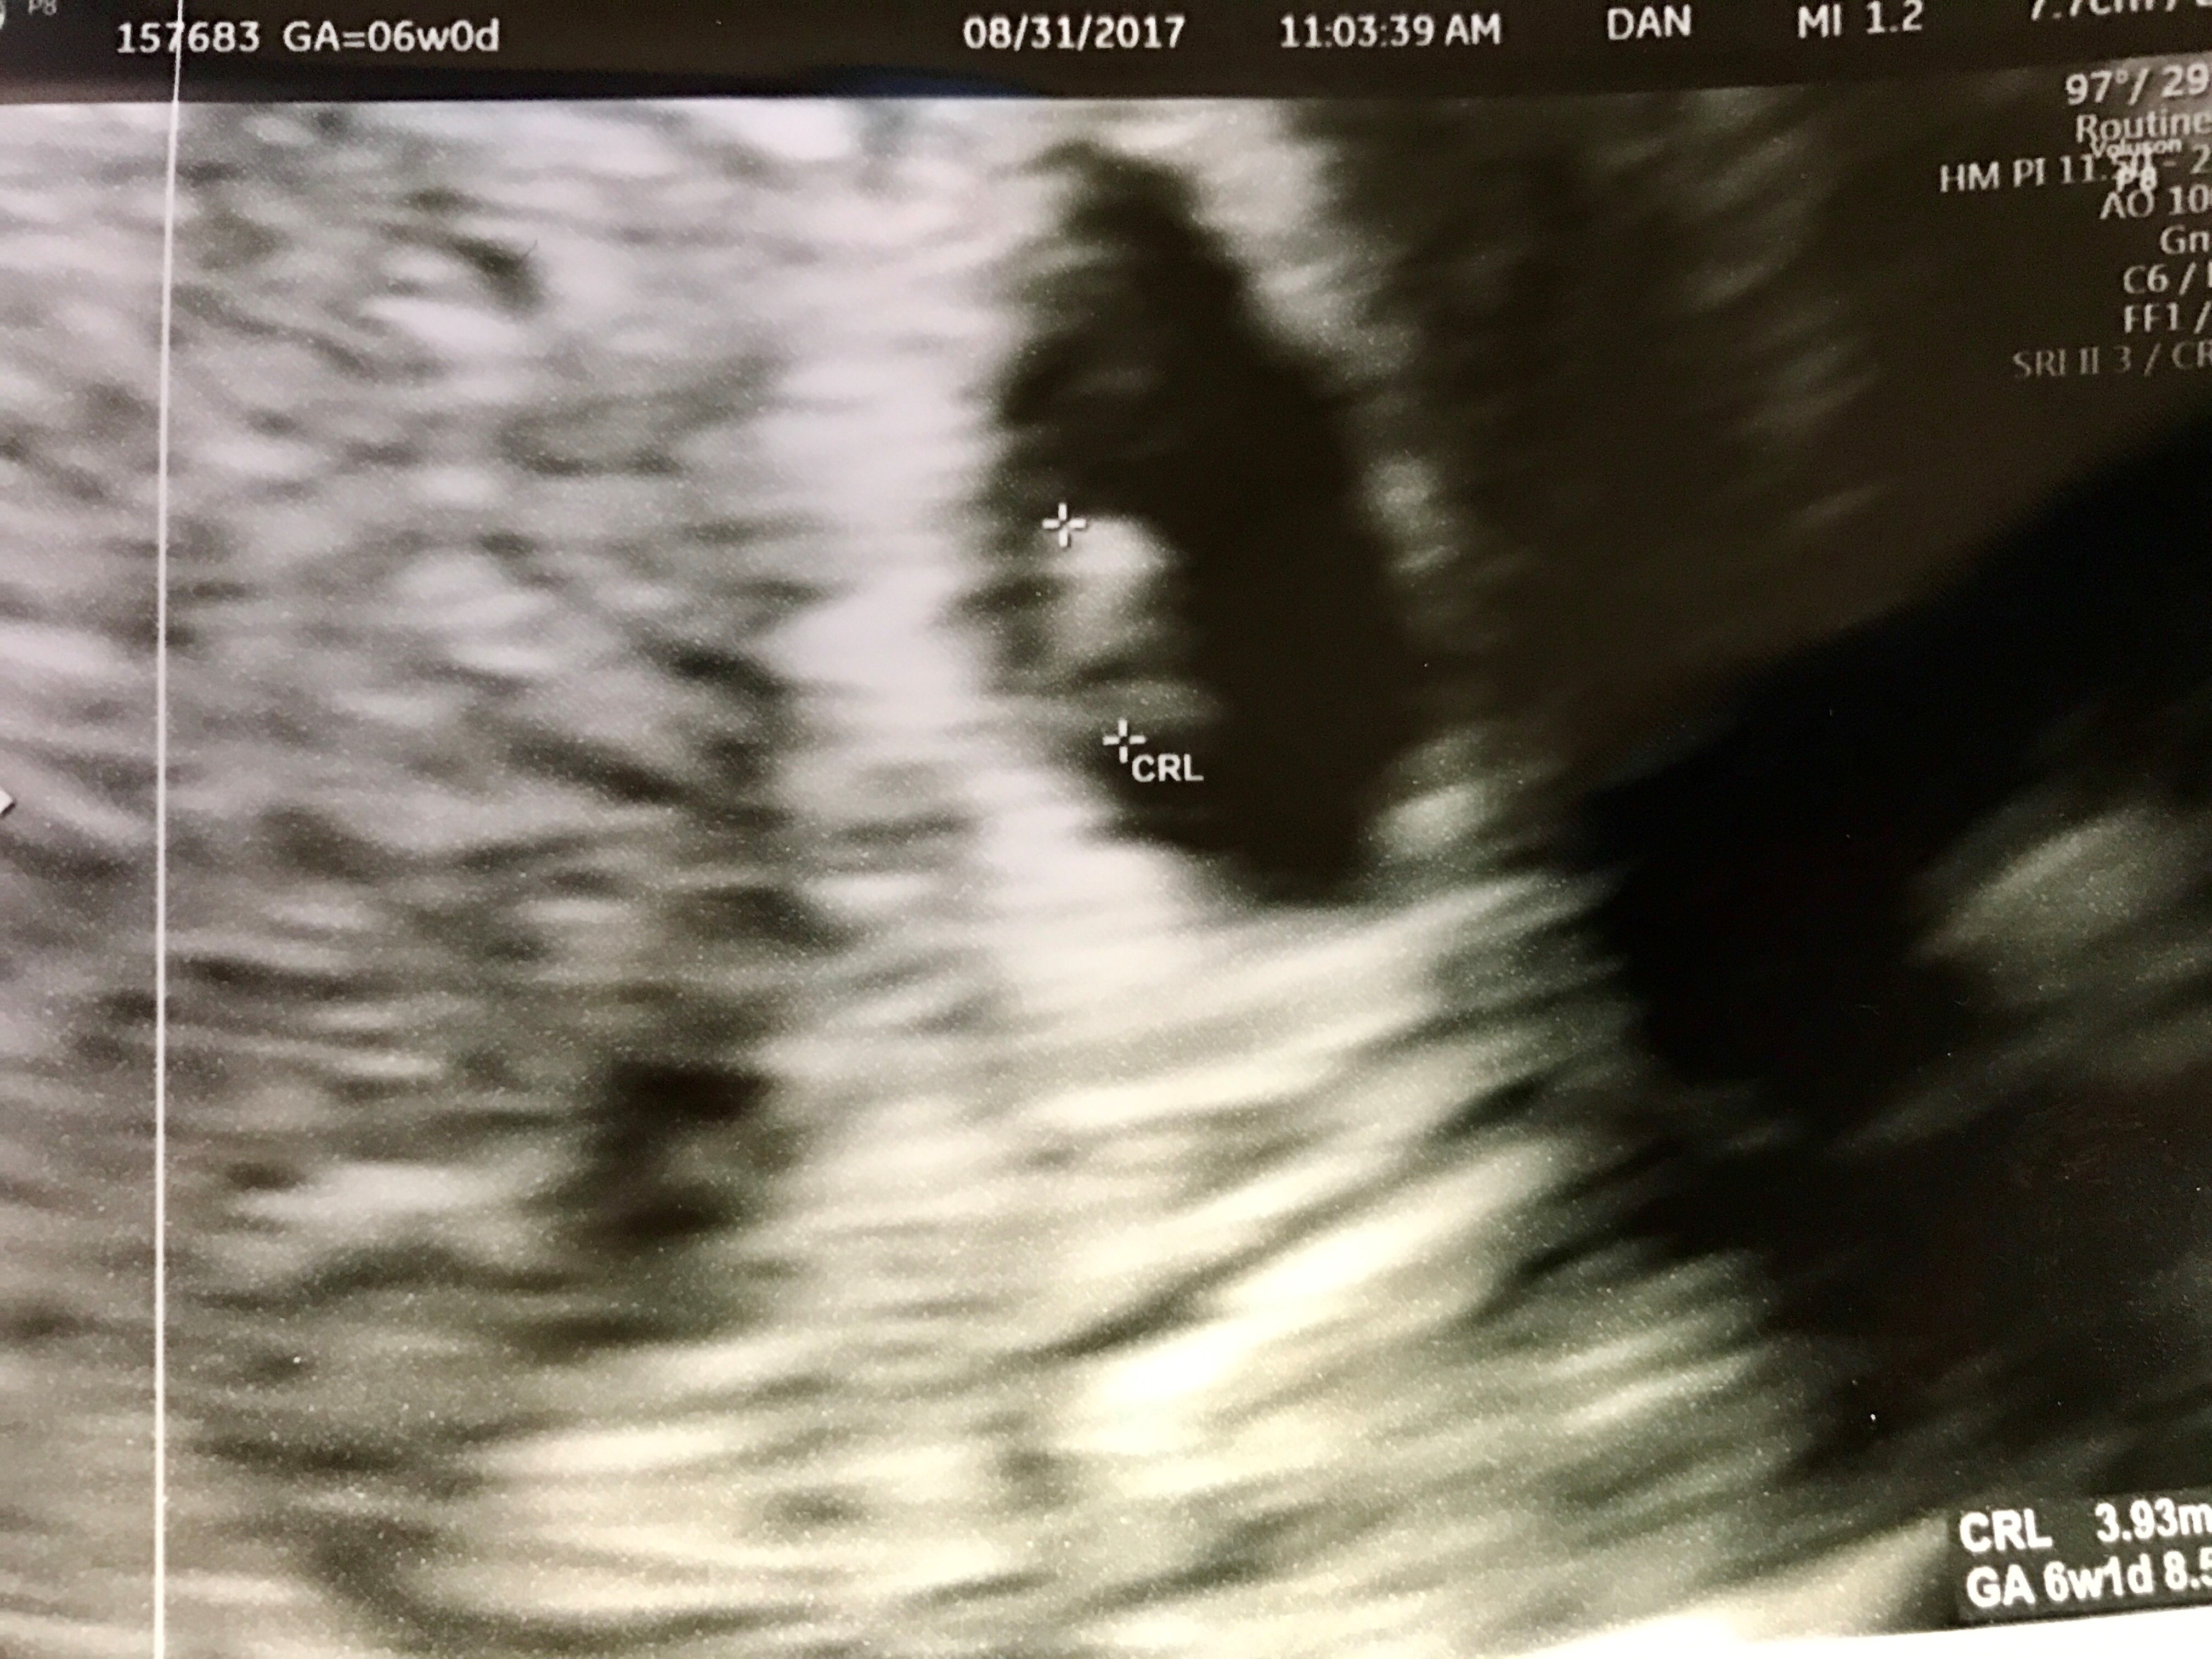

Kyle’s new company has some really great insurance, you see, and through it, we were able to cover PGS for our remaining embryos from the cycle that gave us Isaac and Carrie. Unbelievably, six of the seven embryos were healthy and there are exactly three boys and three girls.

Which brings us to the age old question of WTF are we going to do with all of these frozen babies?

I want one more. Not twins, please god not twins. I love the twins so much, and about 50% of the time, I love that they are twins (the other 50%, they are beating the ever loving shit out of each other for reasons that I do not understand, so I’m like, why couldn’t you be born one at a time so we’d have some buffer space?), but I physically could not do twins again. But I’d love one more girl as a coda.

BUT not for a while yet, if we did. Kyle isn’t fully onboard, which is fair because the twins are a LOT right now, and if someone dropped a baby in my lap right at this second, I’d be like, “WHY DO YOU HATE ME SO MUCH????” because I cannot infant right now. If we went ahead with one last transfer, it would be in 2023, no sooner. Too much is going on in 2022, and my health isn’t where it needs to be.

But it’s on the table now, and we didn’t know if it was on the table before. It was a daydream and now it feels like it could happen? I don’t know if it actually will, but it’s there. One last girl.

(if your pregnancy test does this, feel free to curse it out)

(six days past 5 day transfer)